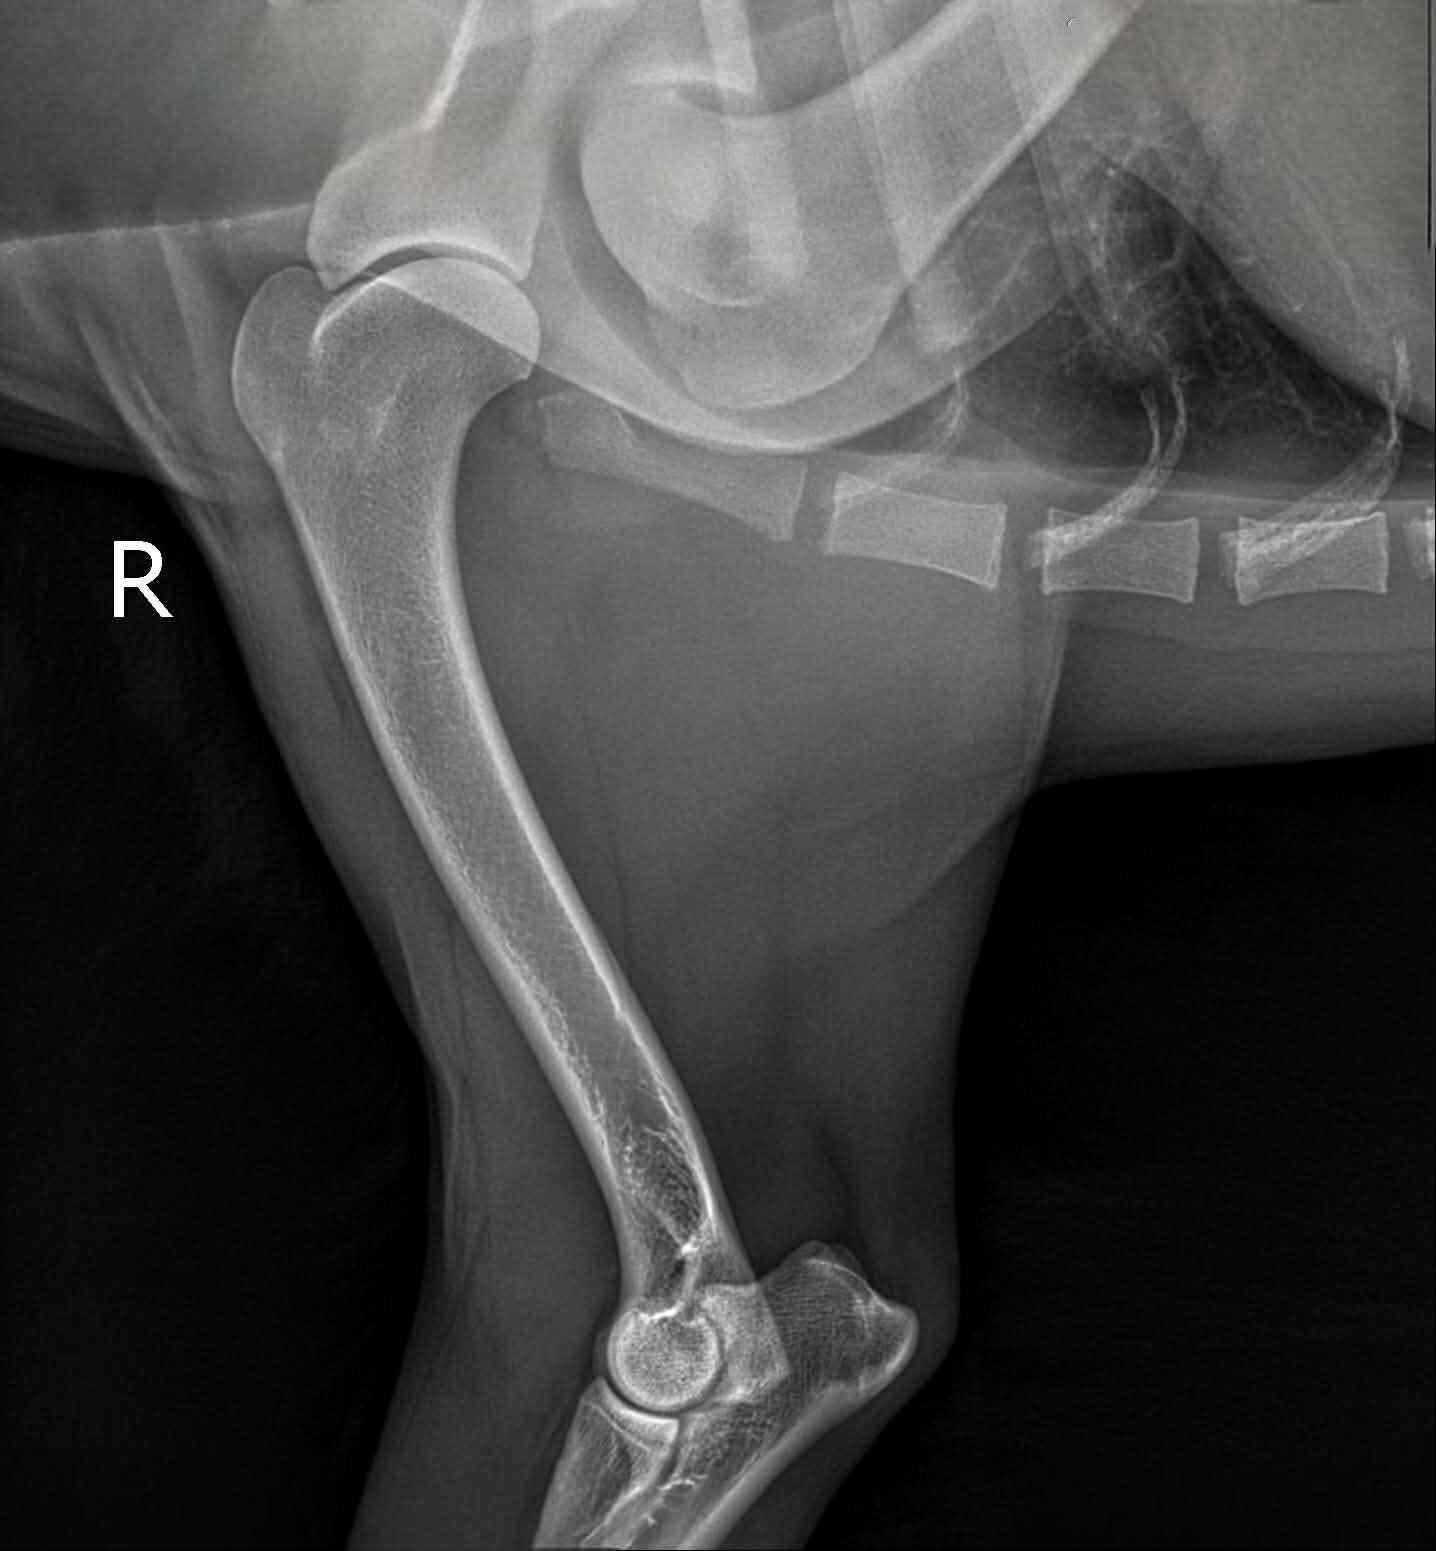

Shoulders - (OCD) Osteochondritis Dissecans

Summary: Shoulder dysplasia, also known as OCD (Osteochondritis Dissecans), is a condition that results from abnormal joint conformation between the humerus and the scapula, causing bone-on-bone motion and degradation, either bilaterally or unilaterally. The presence of this disorder may have symptoms such as mobility issues, limping, and arthritis, similar to other orthopedic disorders. Surgery and/or supportive care may be available options for dogs diagnosed with this condition. With OCD specifically, there is abnormal development in the joint cartilage. OCD can form in other joints as well, but more commonly in shoulders.

Screening: Available in the U.S. through OFA via radiographs submitted by your veterinarian. Each shoulder is evaluated, with affected shoulders either unilaterally or bilaterally affected.